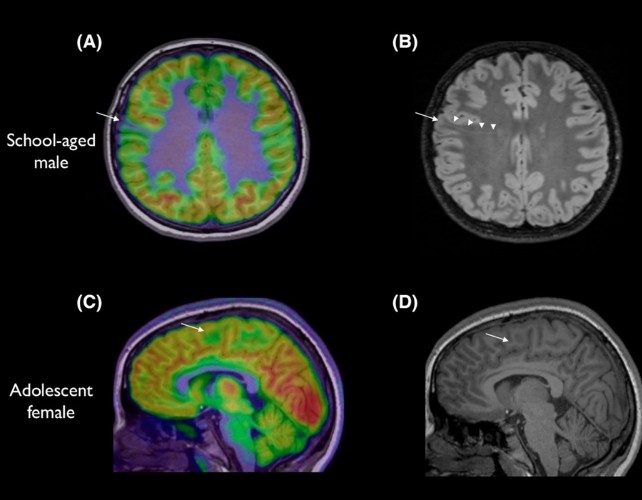

Тимот, предводен од детскиот невролог Ема Макдоналд-Лаурс, ѝ даде на вештачката интелигенција снимки од мозоци на деца, за да може да детектира лезии со големина на боровинка или дури и помали. Таа објаснува: „Тие често се пропуштаат и многу деца не се разгледуваат како кандидати за хирургија. Оваа алатка не ги заменува лекарите, но е детектив кој ни помага побрзо да ги составиме делчињата од сложувалката и да понудиме можност за операција со потенцијално животна промена.“

Во студијата, 80% од децата со кортикална дисплазија и фокална епилепсија веќе имале МРИ што била оценета како „нормална“. Со помош на вештачката интелигенција – преку анализа на МРИ и ПЕТ снимки – алатката успеала да детектира лезии со точност од 94% кај една група и 91% кај друга. Од 17 деца во првата група, 12 биле оперирани, а 11 од нив веќе немаат напади. Следната цел е тестирање на алатката во реални болнички услови кај нови пациенти.